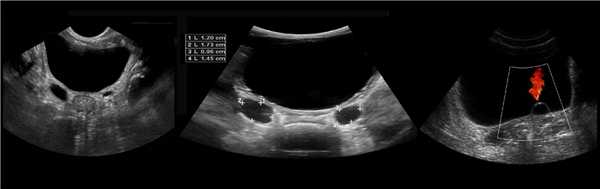

Бывает колонна Бертини врезается в центральную часть почки, разделяя ее полно или неполно на две части. Такая паренхиматозная перемычка — это паренхима полюса одной из эмбриональных долек, которые сливаясь образуют почку; состоит из коры, пирамид, колонн Бертини — все элементы без признаков гипертрофии или дисплазии. Термин гипертрофия колонны Бертини не отражает морфологию структуры, точнее считать данное образование паренхиматозной перемычкой.

Рисунок. На УЗИ округлое образование разделяет почечный синус на два сегмента с общей лоханкой; междолевые артерии огибают образование; эхогенность и интенсивность сосудистого рисунка внутри близка корковой зоне. Заключение: Гипертрофия колонны Бертини или неполная паренхиматозная перемычка. Это вариант нормального строения почки. Термин «неполное удвоение ЧЛК» неверный, т.к. неполная паренхиматозная перемычка не является признаком удвоения ЧЛК.

Рисунок. На УЗИ синус почки разделяет полная паренхиматозная перемычка (1, 2). В таких случаях разграничить удвоение почки от гипертрофии колонны Бертини поможет экскреторная урография. Удвоенная почка покрыта общей фиброзной капсулой. Полное удвоение предполагает наличие двух лоханок, двух мочеточников и двух сосудистых пучков. Неполноудвоенная почка (3) питается одним сосудистым пучком, мочеточник может быть удвоен вверху и впадать в мочевой пузырь одним или двумя устьями. Удвоение ЧЛК и мочеточников — фактор риска развития патологии (пиелонефрита, гидронефроза и др.).